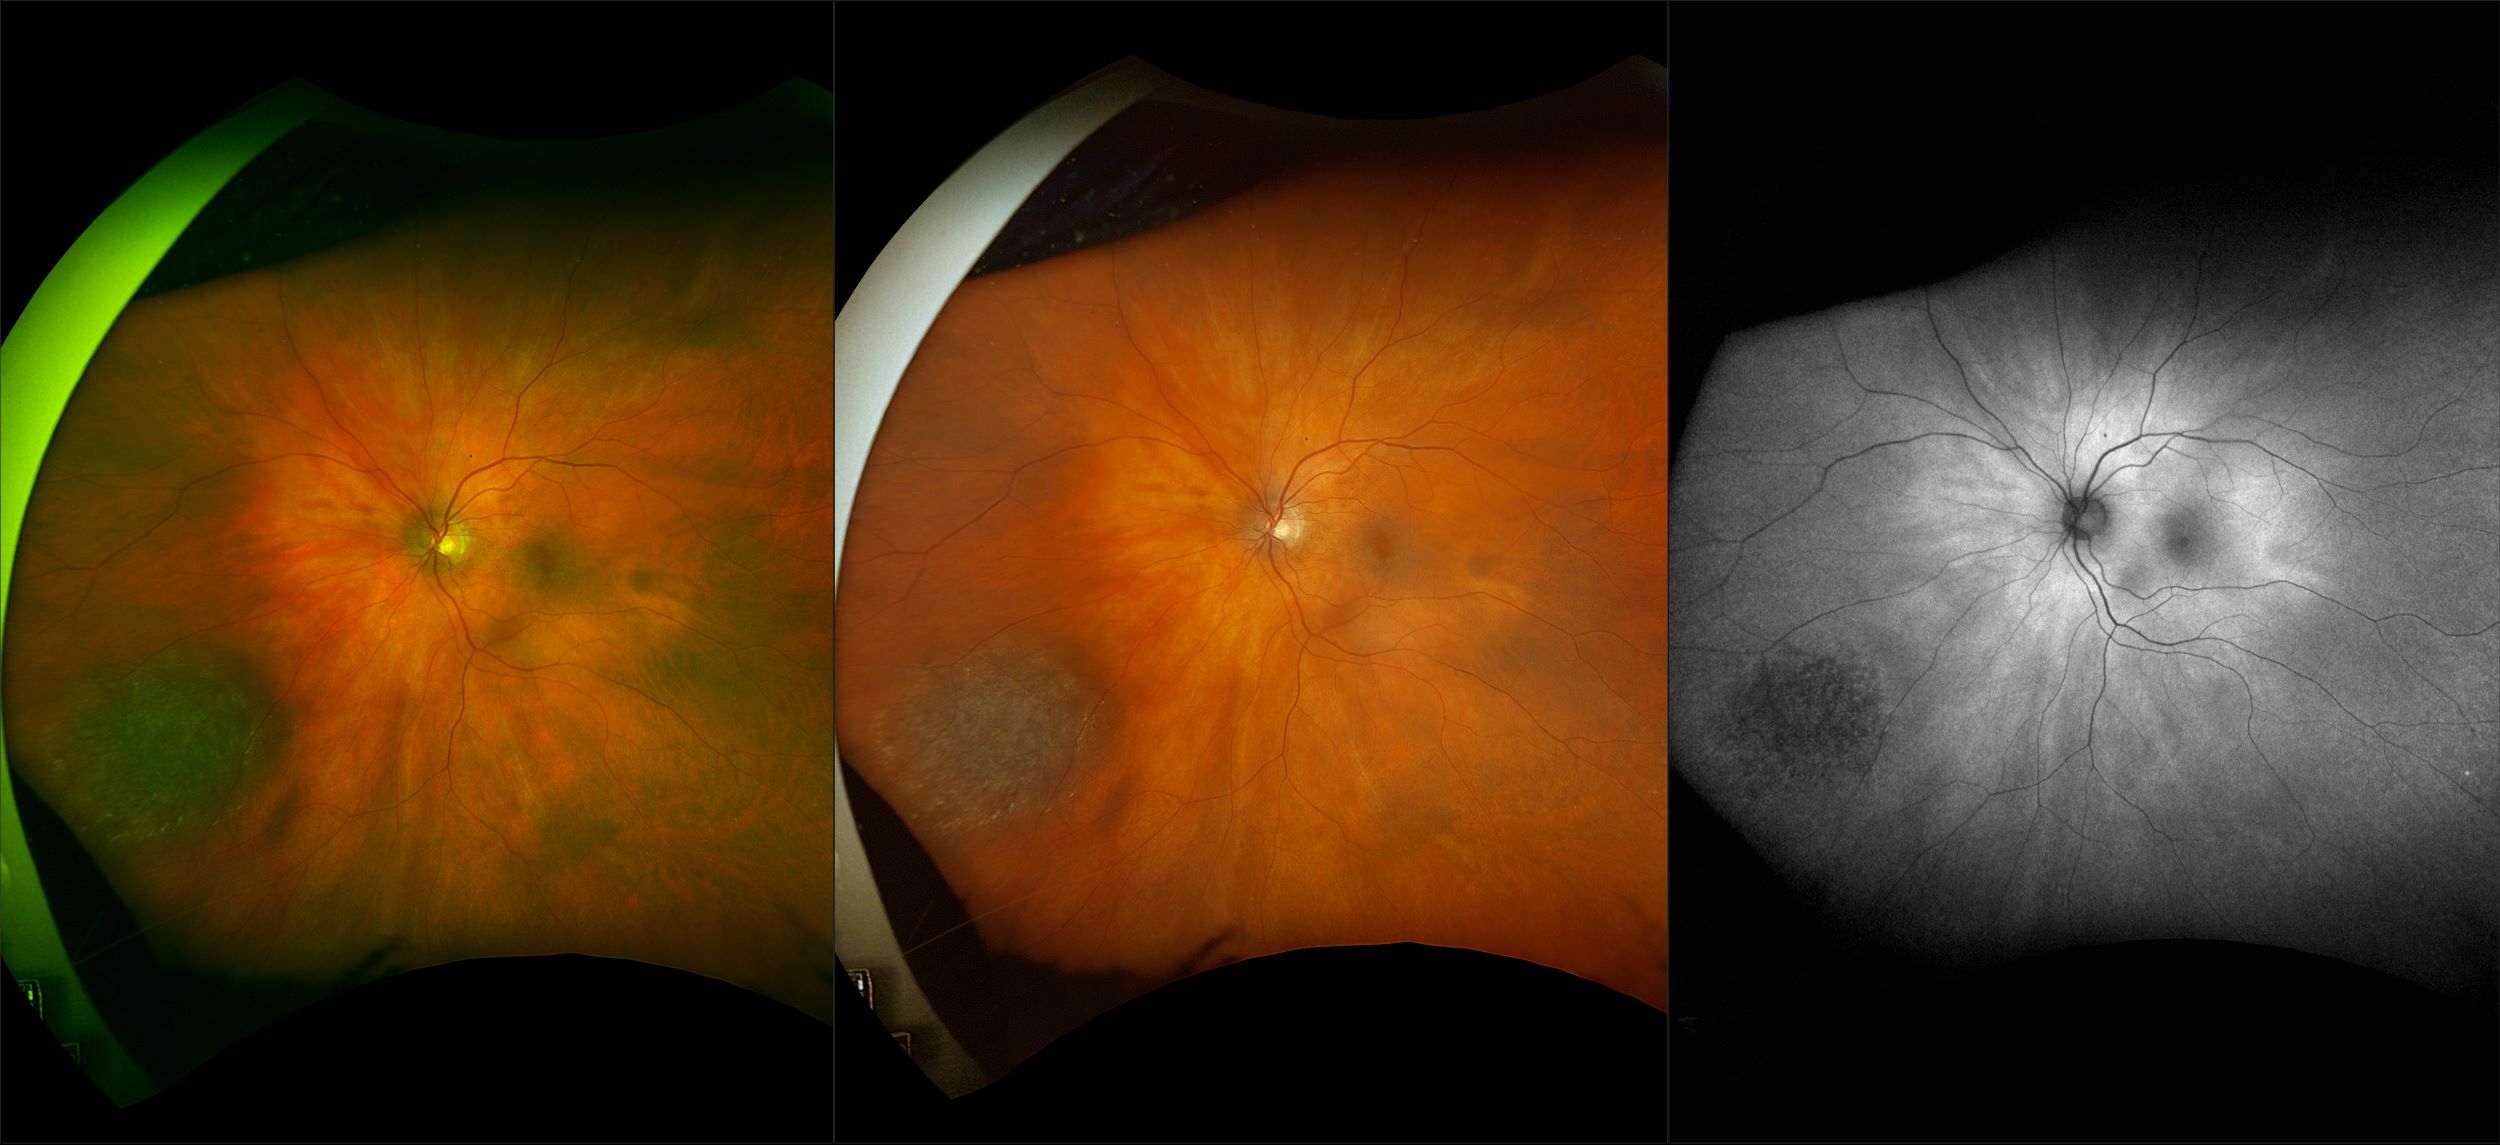

California - Choroidal Nevus, RG, AF

A choroidal nevus is simply an accumulation of melanocytes in the choroid. They are a space occupying mass or a benign melanoma. Choroidal nevi are slate gray in color, have indistinct margins, and may be slightly elevated (1-2 diopters). Since they are in the choroid, they are usually only seen in the red separation and not the green. The green separation may show the RPE degeneration associated with nevi which is seen as pigment mottling and drusen.